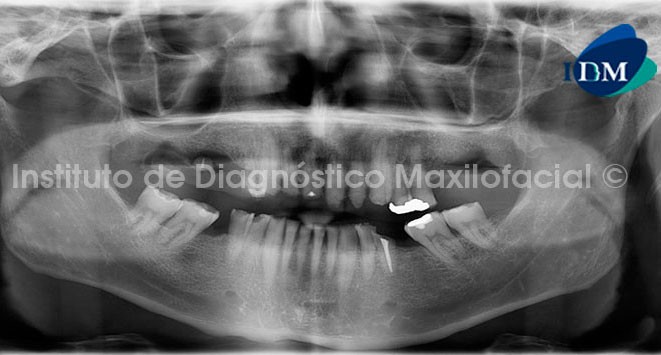

En la reconstrucción tridimensional (Fig. 5) en proyección de máxima intensidad (MIP), se evidencia la perdida de altura dentaria, además de la marcada disminución del esmalte también en caras interproximales presentadose diastemas.